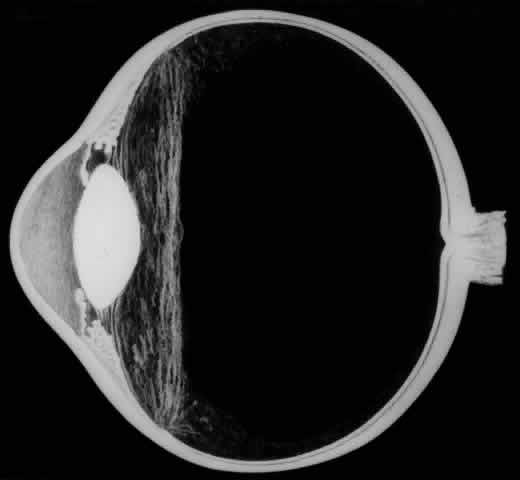

The earliest biomicroscopic changes preceding the development of a giant retinal tear were syneresis and liquefaction of the vitreous gel, converting the posterior and central portions of the vitreous body into a large lacuna (Fig. 14). Later, the anterior gel became condensed, and its posterior aspect formed an equatorially oriented membrane extending across the vitreous cavity (Fig. 15). This membrane did not oscillate with ocular movements, suggesting that it was under tension. Marked contraction of this membrane seems responsible for tearing the retina along the posterior border of the vitreous base (Fig. 16). Liquefied vitreous gel facilitated inversion of the posterior retinal flap (Fig. 17).

Fig. 14. The earliest biomicroscopic change in the vitreous prior to the development of a nontraumatic giant retinal break is liquefaction of the vitreous gel, which converts the central portion of the vitreous gel into a large lacuna.

Fig. 15. In later biomicroscopic changes preceding a nontraumatic giant retinal break, the anterior vitreous gel becomes condensed and a membrane forms its posterior aspect.